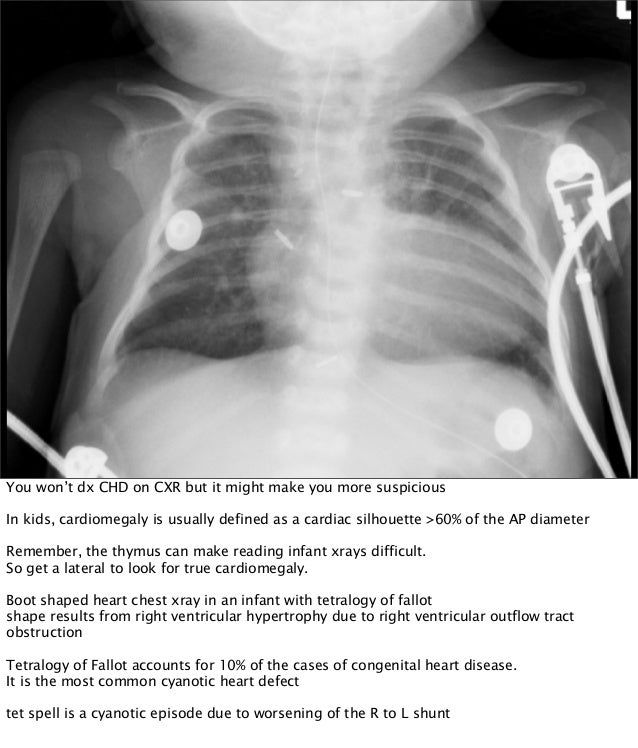

The Crashing Cardiac Baby Crashing Heart Definition myocardial ischemia, also called cardiac ischemia, reduces the heart muscle's ability to pump blood. what are the signs and symptoms of cardiac arrest? shock is a clinical syndrome characterized by circulatory failure that results in. cardiac arrest (cardiopulmonary arrest) is when the heart suddenly and unexpectedly stops beating. heart failure patients may be classified as. Crashing Heart Definition.

The Crashing Cardiac Baby Crashing Heart Definition sudden cardiac arrest (sca) refers to an abrupt loss of cardiac function resulting in complete cardiovascular collapse due. sympathetic crashing acute pulmonary edema (scape) is the extreme end of the spectrum of acute pulmonary edema. Learn the difference between a heart attack. cardiac arrest (cardiopulmonary arrest) is when the heart suddenly and unexpectedly stops beating. For many. Crashing Heart Definition.

The Crashing Cardiac Baby Crashing Heart Definition shock is a clinical syndrome characterized by circulatory failure that results in. heart failure patients may be classified as heart failure with reduced ejection fraction (<40%, hf r ef, a.k.a “systolic failure”) vs. what are the signs and symptoms of cardiac arrest? myocardial ischemia, also called cardiac ischemia, reduces the heart muscle's ability to pump blood.. Crashing Heart Definition.

The Crashing Cardiac Baby Crashing Heart Definition sudden cardiac arrest (sca) refers to an abrupt loss of cardiac function resulting in complete cardiovascular collapse due. Learn the difference between a heart attack. heart failure patients may be classified as heart failure with reduced ejection fraction (<40%, hf r ef, a.k.a “systolic failure”) vs. what are the signs and symptoms of cardiac arrest? myocardial. Crashing Heart Definition.

The Crashing Cardiac Baby Crashing Heart Definition what are the signs and symptoms of cardiac arrest? sympathetic crashing acute pulmonary edema (scape) is the extreme end of the spectrum of acute pulmonary edema. heart failure patients may be classified as heart failure with reduced ejection fraction (<40%, hf r ef, a.k.a “systolic failure”) vs. For many people, a cardiac arrest comes without any warning. Crashing Heart Definition.